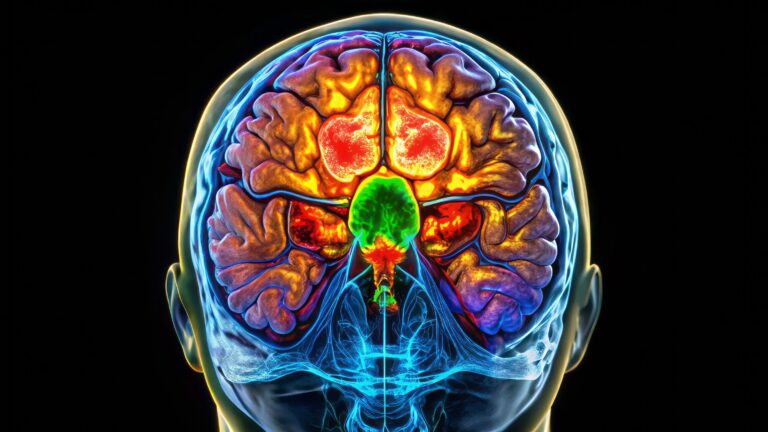

Explore the future of healthcare with microrobots for medical use, offering targeted drug delivery and improved navigation.